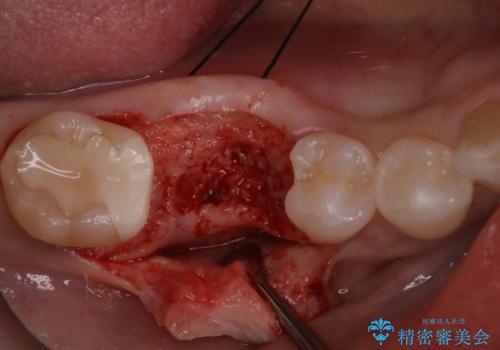

- 他院で抜歯されて、今後どうしたらいいのかを相談された患者様です。

抜歯を行った後は、Br、義歯、インプラント、何もしないという選択肢のメリットデメリットを説明させていただき患者様がインプラント治療を希望されたので今回治療させていただくことになりました。

二回の手術を終えて最終的な被せ物が入るまで6〜8ヶ月かかると思います。